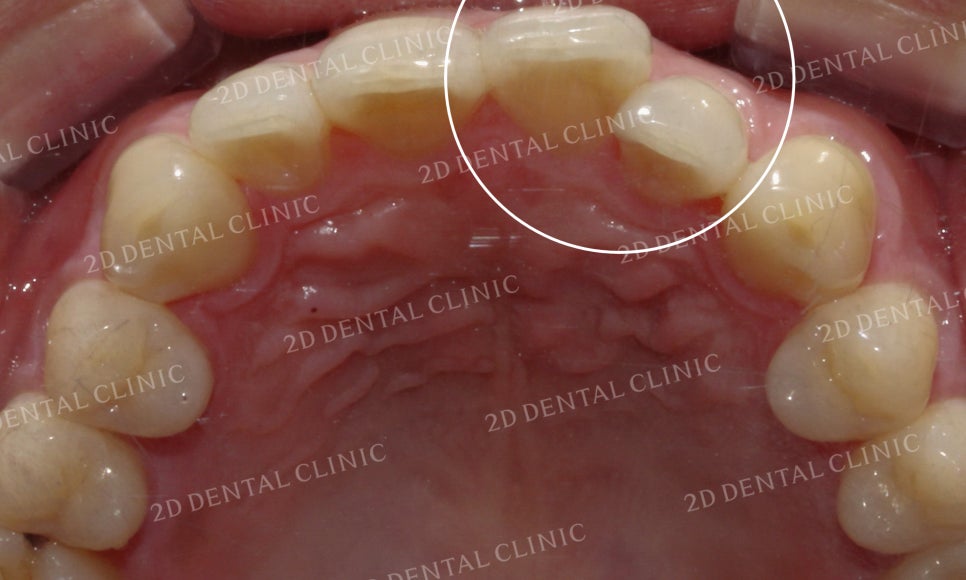

상악 설측면의 사진입니다.

위에서 말했던 것처럼

21번 치아가 회전되어 있어서

측정치가 설측으로 들어와 있는

상황입니다.

상악의 설측면 사진입니다.

표시된 부분의 21번 치아가

유독 회전이 심한 모습이었는데요

이로 인해 측절치가 중절치의

뒤쪽으로 파고들면서

치간에 치석과 플라그가 쌓이고 있는 상태였습니다.

그러나 교정 후 치아가 겹쳐진 부분들이 사라지고

삐뚤거리던 크라우딩도 사라지면서

가지런해진 치아들을 볼 수 있습니다.